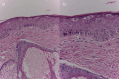

Congenital epidermodysplasia verruciformis (CEV) is a Genodermatosis linked to different inheritance patterns and mutations of the EVER1/TMC6 and EVER2/TMC8 genes. There is an acquired form (AEV) associated with immunodeficiency states, including human immunodeficiency virus (HIV) infection; however, the literature about AEV is limited and imprecise, so a systematic review was performed. A search of the main databases from 1975 to 2021 identified 126 studies, of which 80 met the inclusion criteria. The diagnosis of AEV is complex due to atypical manifestations and locations, it requires a mean follow-up of 7 years, and the lesions do not change with ART therapy, CD4 count, or viral load. Histopathological findings are variable depending on the location of the lesions. HPV 5 remains the serotype most frequently associated with AEV and CEV, although HPV 20 is more frequent than HPV 8 in AEV. Most treatments have low efficacy, the most described are glycolic acid 15%, 5-fluorouracil 5%, imiquimod 5%, and topical retinoids all of them in monotherapy or combined with cryotherapy. Other alternatives include topical cidofovir and systemic retinoids with variable results. The oncologic prognosis is still inconclusive; however, the development of squamous cell carcinoma and melanoma are frankly lower concerning CEV. This review opens new opportunities for future research. Additionally, we provide clear and useful key points for the practice of dermatologists and all professionals treating HIV patients around the world.